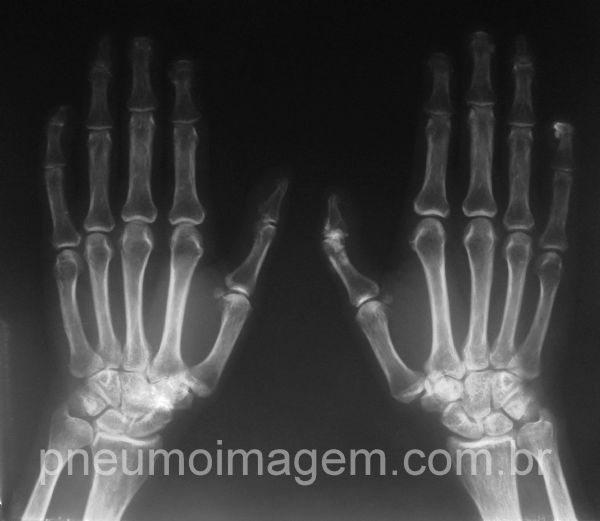

Reabsorção das falanges distais.